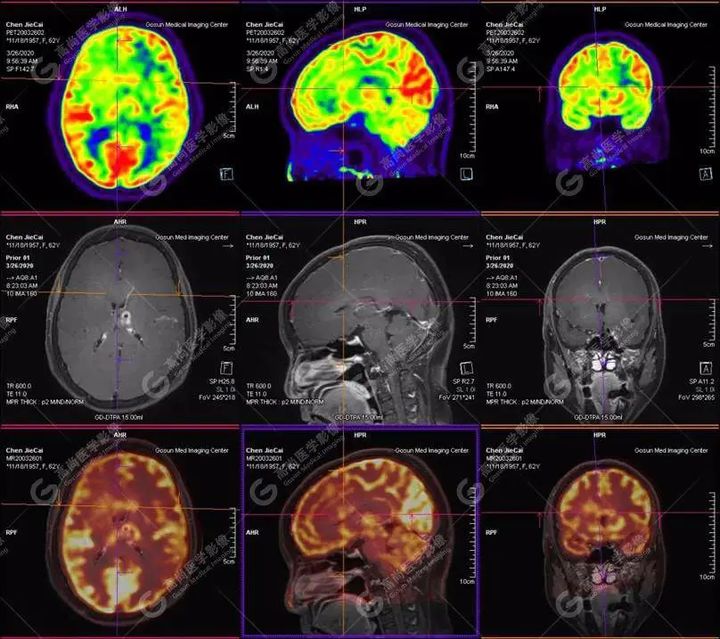

【高尚醫(yī)療影像】【多模態(tài)影像】顱內(nèi)淋巴瘤PET-MR融合顯像1例

【病史摘要】患者,女,62歲

失眠伴記憶力減退近一月入院檢查,無(wú)頭痛、嘔吐、四肢活動(dòng)正常

外院CT提示,顱內(nèi)多發(fā)占位,轉(zhuǎn)移瘤可能

左側(cè)顳葉、頂葉、左側(cè)基底節(jié)區(qū)及胼胝體部多發(fā)結(jié)節(jié)狀高代謝病灶,部分合并囊變、出血,MR平掃+增強(qiáng)示不均勻輕、中度強(qiáng)化,綜合考慮為顱內(nèi)原發(fā)惡性腫瘤,以淋巴瘤可能性大

【病理結(jié)果】彌漫大B細(xì)胞淋巴瘤

淋巴瘤病變多位于中線兩旁的深部腦實(shí)質(zhì)、側(cè)腦室周圍及腦表面,甚少累及腦膜和顱骨,幕上多于幕下,呈分葉狀或握拳狀,水腫及占位效應(yīng)較輕,部分病灶內(nèi)可見(jiàn)囊變、出血及其邊緣的硬環(huán)征、尖角征、臍凹征,增強(qiáng)掃描呈現(xiàn)的“臍凹征或者“握拳征”是淋巴瘤較為特征性的一個(gè)表現(xiàn)。

18F-FDG PET PET顯像中呈明顯高代謝病灶。

顱內(nèi)惡性淋巴瘤對(duì)18F-FDG的攝取率很高,一般SUV在5~10以上,18F-FDGPET顯像中攝取明顯高于正常腦皮層,因此具有特征性。

PET/CT-MR檢查是原發(fā)顱內(nèi)惡性淋巴瘤的重要檢查方法,能有效提高診斷正確率;在早期發(fā)現(xiàn)、準(zhǔn)確分期、放化療后檢測(cè)具有極重要的作用。